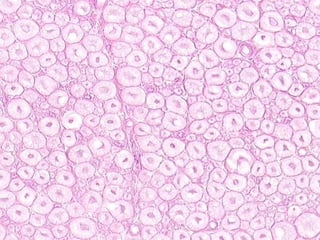

• #17 Slam dunk classical appearance of skeletal muscle. Why is skeletal muscle or voluntary striated muscle a better name for this than just striated muscle? Ans: Because cardiac muscle also has striations. Logs on a fireplace may overlap with each other, even diagonally a bit, but they do NOT fuse.

• #18 Is the peripheral nature of skeletal muscle nuclei more apparent from cross or longitudinal sections? Ans: Cross Why? Ans: Simple geometry! Are striations better seen on cross or longitudinal sections? Ans: Longitudinal Why? Ans: Simple geometry again!